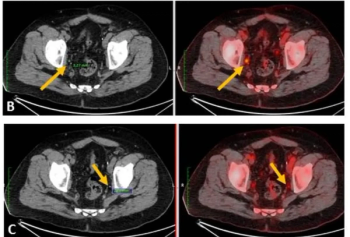

In patients who had at least four cycles of 177Lu-PSMA-I&T for mCRPC, new research shows that a 10 percent or greater decrease in total kidney volume on CT at six months has a 90 percent AUC for predicting estimated glomerular filtration rates (eGFRs) of 30 percent or greater at one year.